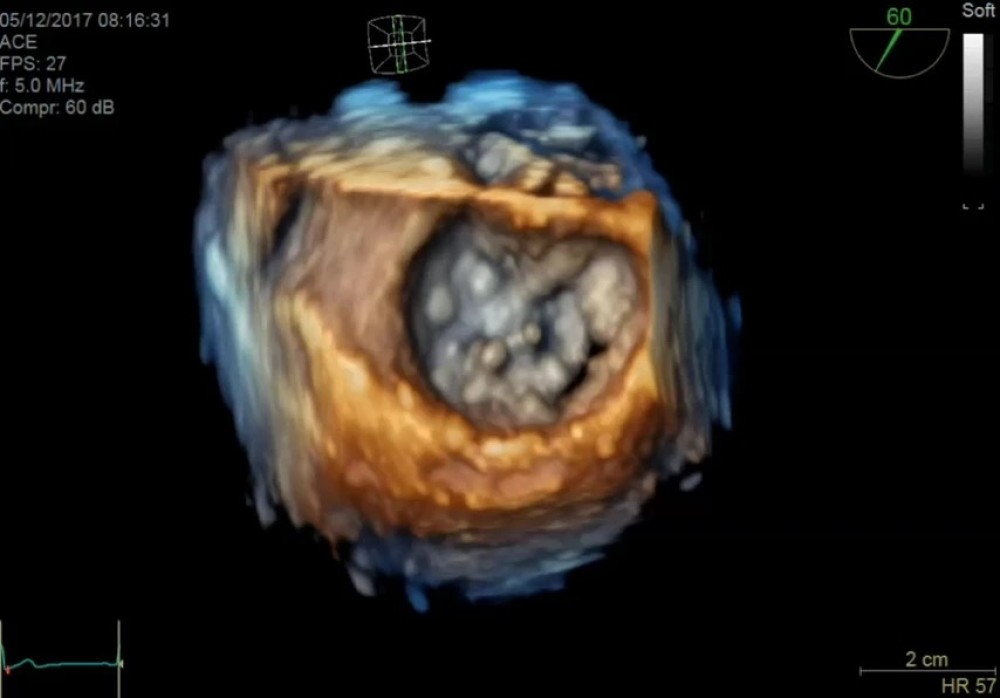

4D görüntüləmə (transtorakal və transözofageal prob dəstəkləndikdə)

HDlive — təkmilləşdirilmiş 4D vizualizasiya texnologiyası

4D Auto LVQ — sol ventrikulun 4D avtomatik kvantitativ analizi

Transözofageal və volumetrik prob dəstəyi

GE Vivid S70N Dimension — mütəxəssis kardiologiyası üçün nəzərdə tutulmuş inkişaf etmiş ultrasəs sistemi. Bu model təkmilləşdirilmiş 4D ekokardioqrafiya funksiyalarına malikdir və matriks  (TEE) problarını dəstəkləyir. Sistem həmçinin kvantitativ həcmli məlumatların təhlili və qiymətləndirilməsi üçün geniş alətlər toplusunu təmin edir.

cSound platforması əsasında işləyən Vivid S70N Dimension ürək və damar strukturlarının yüksək dəqiqlikli görüntülənməsini təmin edir, beləliklə kardiologiya üzrə mütəxəssis mərkəzlər, funksional diaqnostika şöbələri və yüksək diaqnostik dəqiqlik tələb edən tibb müəssisələri üçün ideal seçimdir.